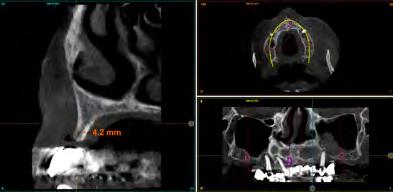

Fueron reclutados de forma retrospectiva, pacientes que presentasen atrofia ósea extrema mixta, tanto en maxilar como en mandíbula y en los que se insertasen implantes extracortos (5.5 y 6.5 mm) y de plataforma reducida de 3 mm, durante un periodo comprendido entre junio de 2020 y junio de 2021. Antes de la inserción de los implantes se utilizó una premedicación antibiótica consistente en amoxicilina 2 g vía oral una hora antes de la intervención y paracetamol 1 g vía oral (como analgésico). Posteriormente los pacientes prosiguieron con un tratamiento de amoxicilina 500-750 mg vía oral cada 8 horas (según peso) durante 5 días. Todos los pacientes fueron estudiados antes de la inserción de los implantes mediante modelos diagnósticos, exploración intraoral y realización de un TAC dental (cone-beam) analizado posteriormente mediante un software específico (BTI-Scan III).

Figura 8-11. Imágenes de la planificación del cone-beam dentral tras el cierre de los tejidos blandos (inserción temprana de los implantes). En ellos observamos la planificación de los implantes de 6.5 mm de longitud y de diámetro reducido y plataforma 3.0 que van a ser empleados.

Dentista y Paciente 18 Calidad y dirección